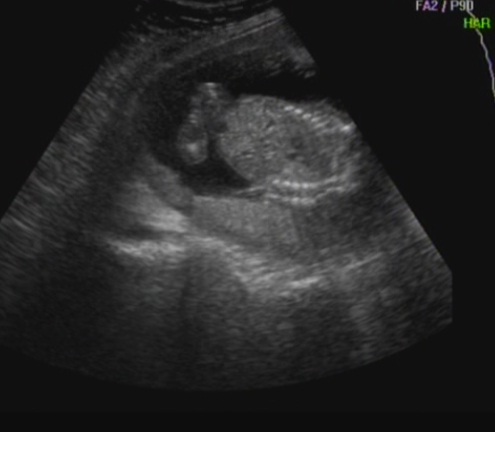

Örülök, hogy még mindig láááááány!!!! Nálunk annyira egyértelmű volt a 16. heti UH-n, hogy ha nem láttak semmit, akkor lassan kezdd elhinni!